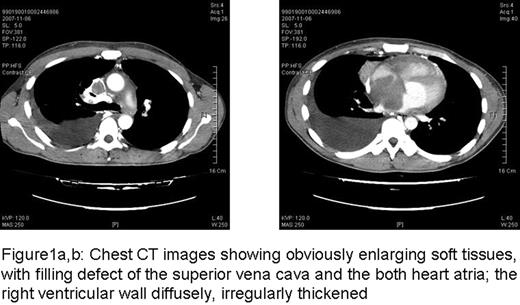

A 33-year-old man of Asian descent was admitted to our hospital 3 years ago with a main complaint of palpitations for 7 months. There was no fever, no cough, no gain or loss of weight, no night sweats, no medical history of allergic diseases or contact with parasites. Physical examination showed marked edema in the neck and upper chest, and the hepatojugular reflux was positive. There was no change in skin appearance or hepatosplenomegaly. A soft rubbery, non-tender lymph node (1×2cm) was palpated in the left axillary area. The laboratory data showed mild eosinophilia (leukocyte count 6000 /ul with eosinophils 582/ul). The serum IgE concentration was increased (1,250 U/ml). Serological tests for HBsAg, anti-HCV, anti-HIV, and antibodies for distoma pulmonala, distoma japonicum, schistosome, bladder worm, sparganum, trichina cystica and filarial were negative, however toxoplasma gondii antibody IgG was positive, while the IgM was negative. Antinuclear antibodies were all negative. Echocardiogram revealed a mass (7.1×7.0×5.5cm) displacing the base of the heart and involving both atria. CT showed enlarged biaxillary lymph nodes and a large mediastinal mass extending into both atria and obstructing the superior vena cava with right ventricular hypertrophy (Fig.1a, b). Positron emission tomography (18F-FDG-PET) scan indicated negative fluorodeoxyglucose (FDG) uptake in the lymph nodes, spleen and liver. Biopsy of an enlarged right axillary lymph node was performed and the pathology revealed a normal preserved nodal architecture with proliferation of lymphoid follicles infiltrated by abundant eosinophils partially forming eosinophilic microabscesses. CD20 staining was positive. The bone marrow examination indicated normal cellularity except a little increase of eosinophils at 7.5%. Biopsy of the cardiac mass was not performed due to technical challenges related to its anatomical location. Based on the clinical and laboratory findings, a diagnosis of Kimura disease was established. Treatment was started with a low dose of oral prednisone 20–30mg/d. After treatment, the enlarged lymph nodes diminished gradually. However, 4 months later, echocardiogram showed the mediastinal mass remained, with two new masses (left 5.4×3.2cm, right 4.3×2.6cm) attached to the atrial septum respectively (Fig2). Prednisone was gradually increased to 50mg/d. 3 months later, the patient was admitted to hospital with chest pain and shortness of breath. Thoracic CT showed severe obstruction of the right middle lobe bronchus by the enlarged mediastinal mass. A bone marrow smear and flow cytometric analysis did not show any clonal hematopoietic abnormality. The echocardiogram remained unchanged. Prednisone (40mg/d) was re-administered but the patient's situation was getting worse quickly. He developed dyspnea and hypoxemia, apparent SVCS, edema of the inferior extremities and recurrent arrhythmia. CHOP chemotherapy was initiated (CTX 1.0 dl, VDS 4mg dl, EPI-ADM 60mg dl, DXM 10mg dl-2) but he died due to cardiac and respiratory failure. Kimura's Disease is a distinct clinicopathological entity accompanied by peripheral blood eosinophilia and elevated serum IgE level. Though rare, KD with cardiovascular involvement has been reported in several cases. This kind of involvement is also named as Eosinophilic Myocarditis (EM), occurs in up to 60% of patients diagnosed with hypereosinophilic syndrome (HES). However, this patient only has partial response of prednisone, and relapsed after 9 months therapy with prednisone 20–50 mg/d. Although chemotherapy was added, it was too late to control the progression of disease. This instructive case demonstrates that although Kimura's disease is a benign process, infiltration of eosinophils in multiple organs may result in critical illness and can be fatal. Early intervention and frequent close followup appears essential for controlling disease in KD patients with cardiac or other critical complications.